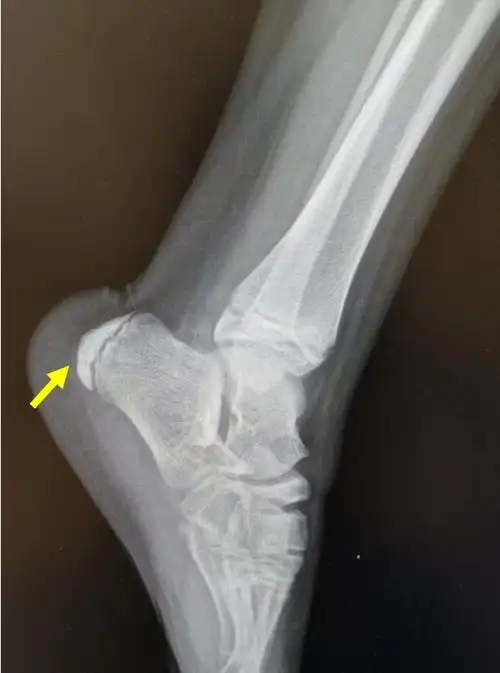

跟骨x线显示跟骨刺综合征

患儿,男,11岁,跟骨骨骺炎,跟骨侧位片可见跟骨骨